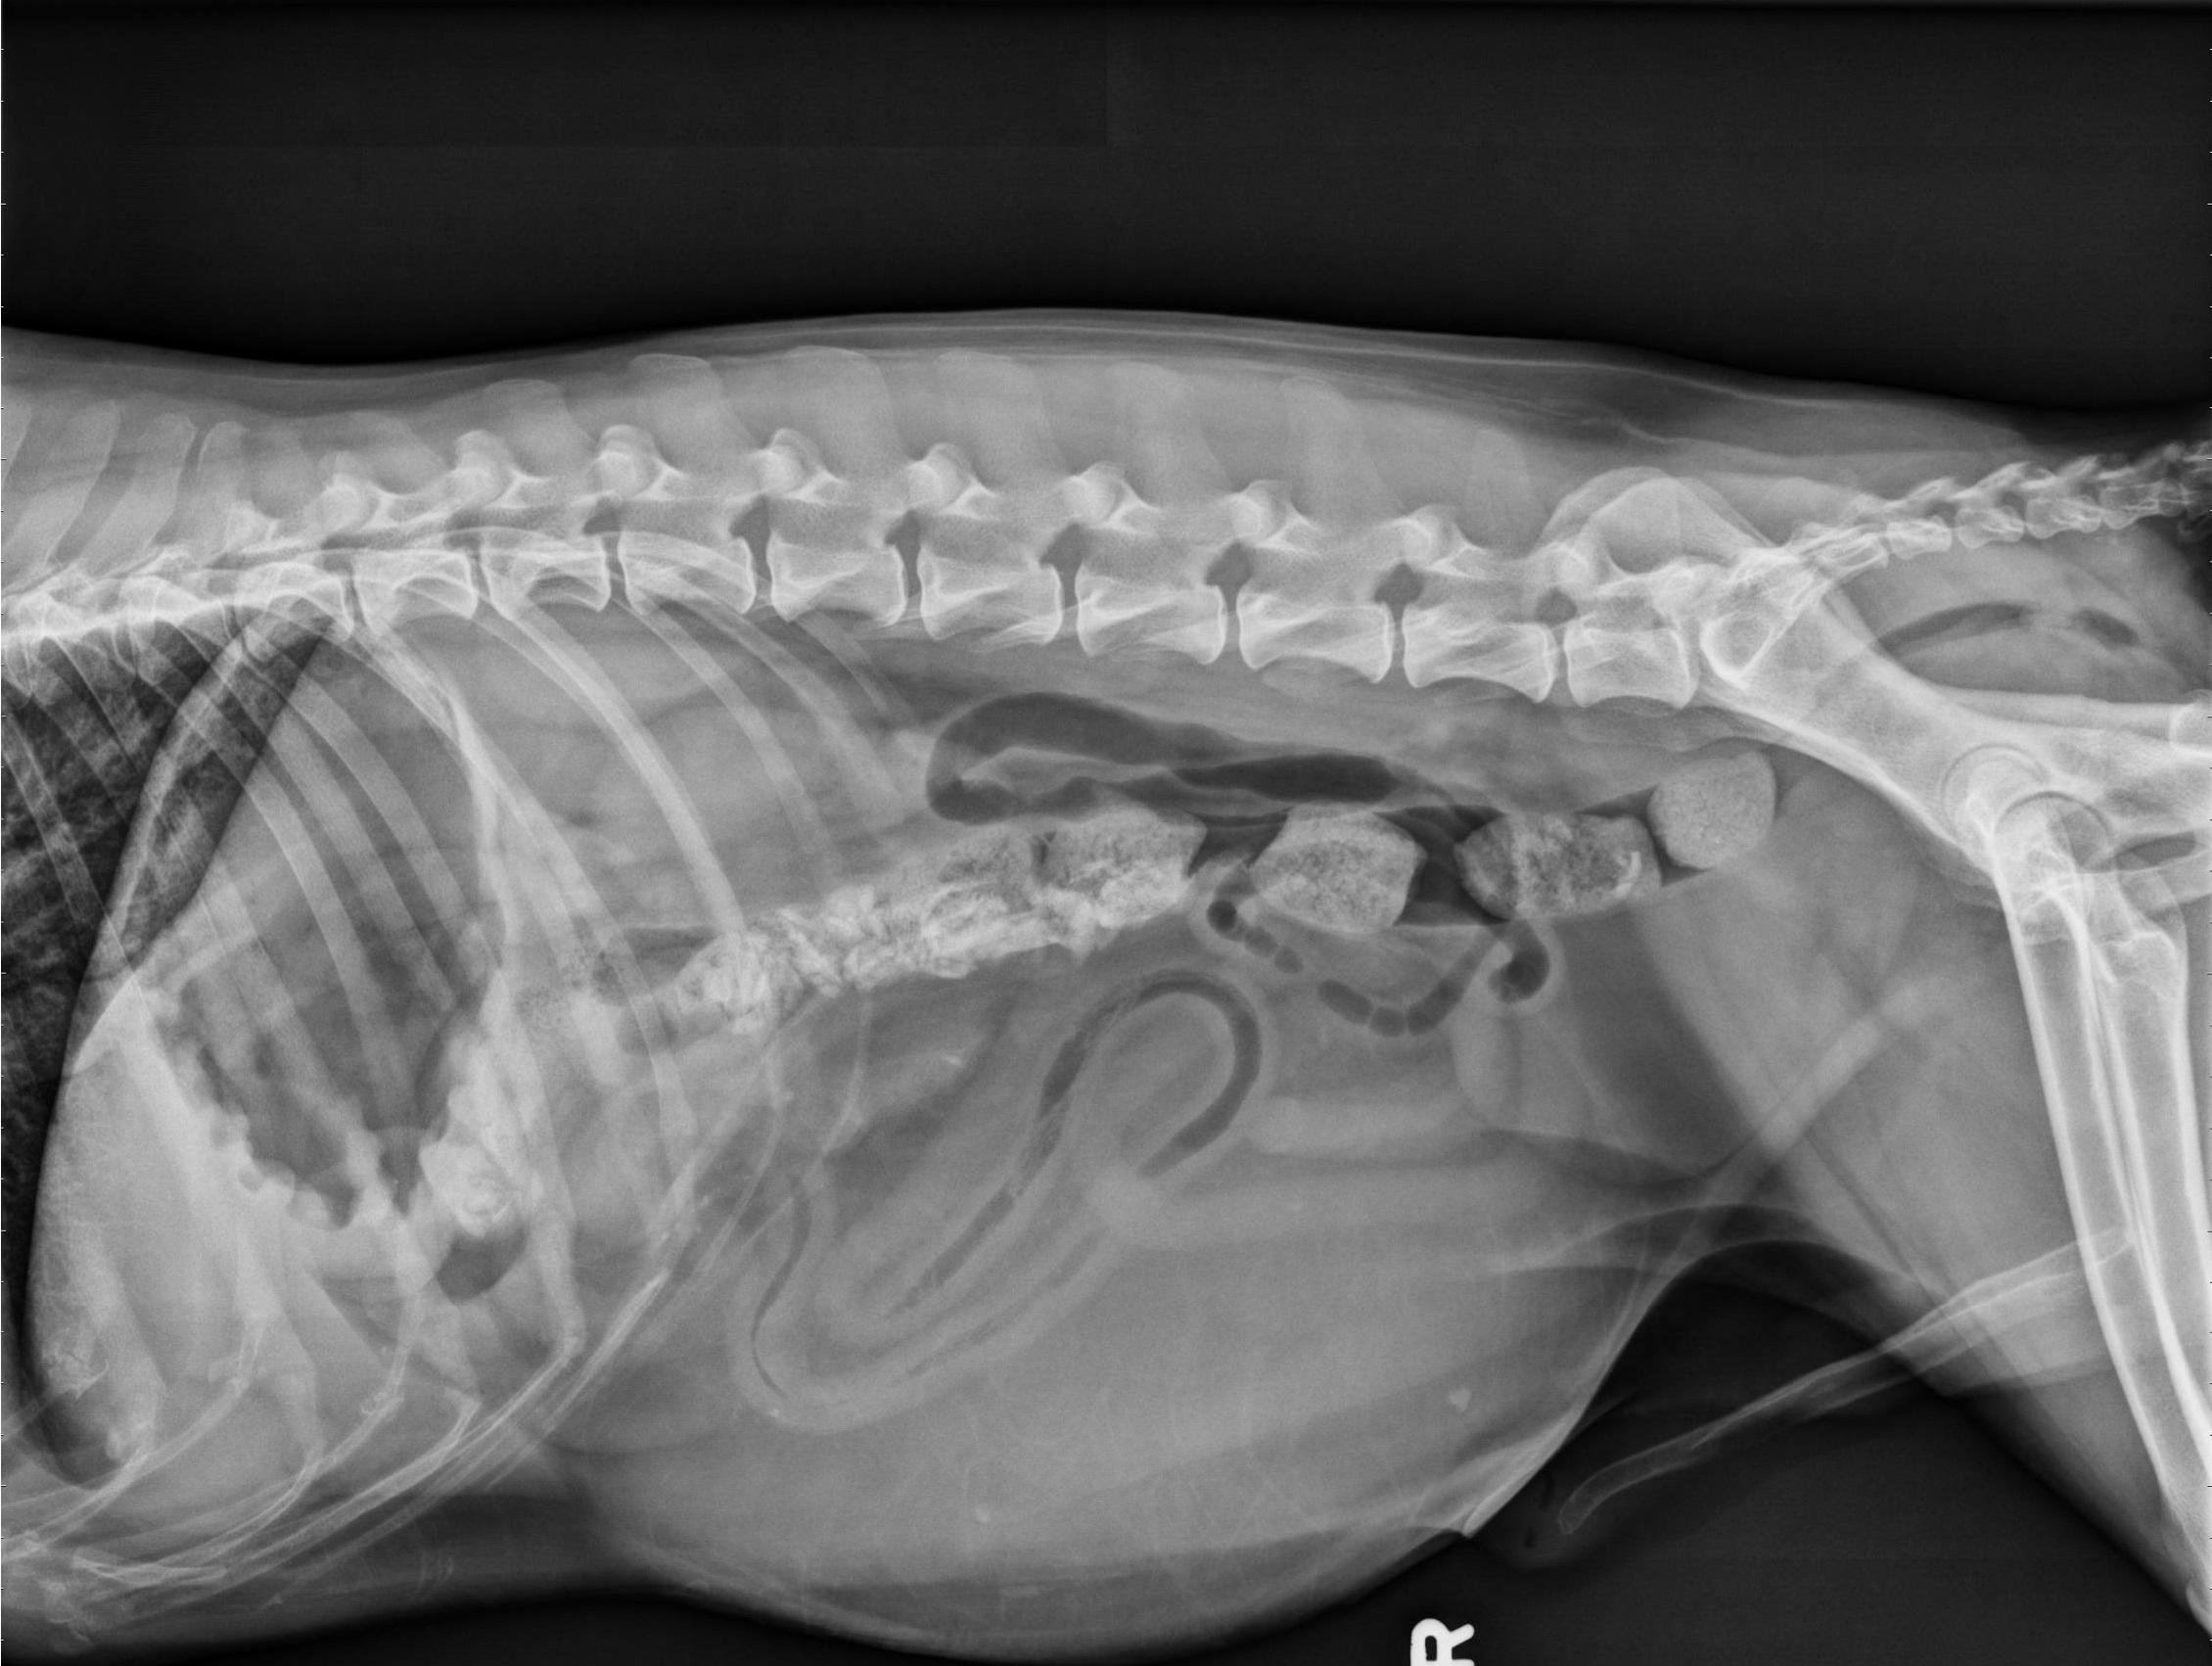

Er is een artefact door natte vacht langs de ventrale buik. De serosale details zijn normaal.

In het linker mid-ventrale abdomen bevindt zich een grote, ovale structuur met vetdensiteit van ongeveer 20 x 15 cm. Deze structuur veroorzaakt een laterale deviatie van de linker buikwand, een naar rechts en dorsaal verplaatste colon en dunne darmen, en een craniale verplaatsing van de staart van de milt.

De maag is matig met gas gevuld. De dunne darmen bevatten diffuus gas en vloeistof/weke delen densiteit en hebben een normale en uniforme diameter. In het colon zijn fusiforme tot rechthoekige botdense structuren zichtbaar.

Lever, milt, nieren en urineblaas zijn normaal.